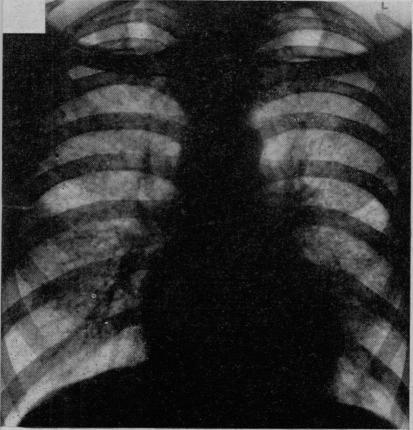

Discussion on sarcoidosis.

Proc R Soc Med. 1956 Oct;49(10):799-806. doi: 10.1177/003591575604901012.